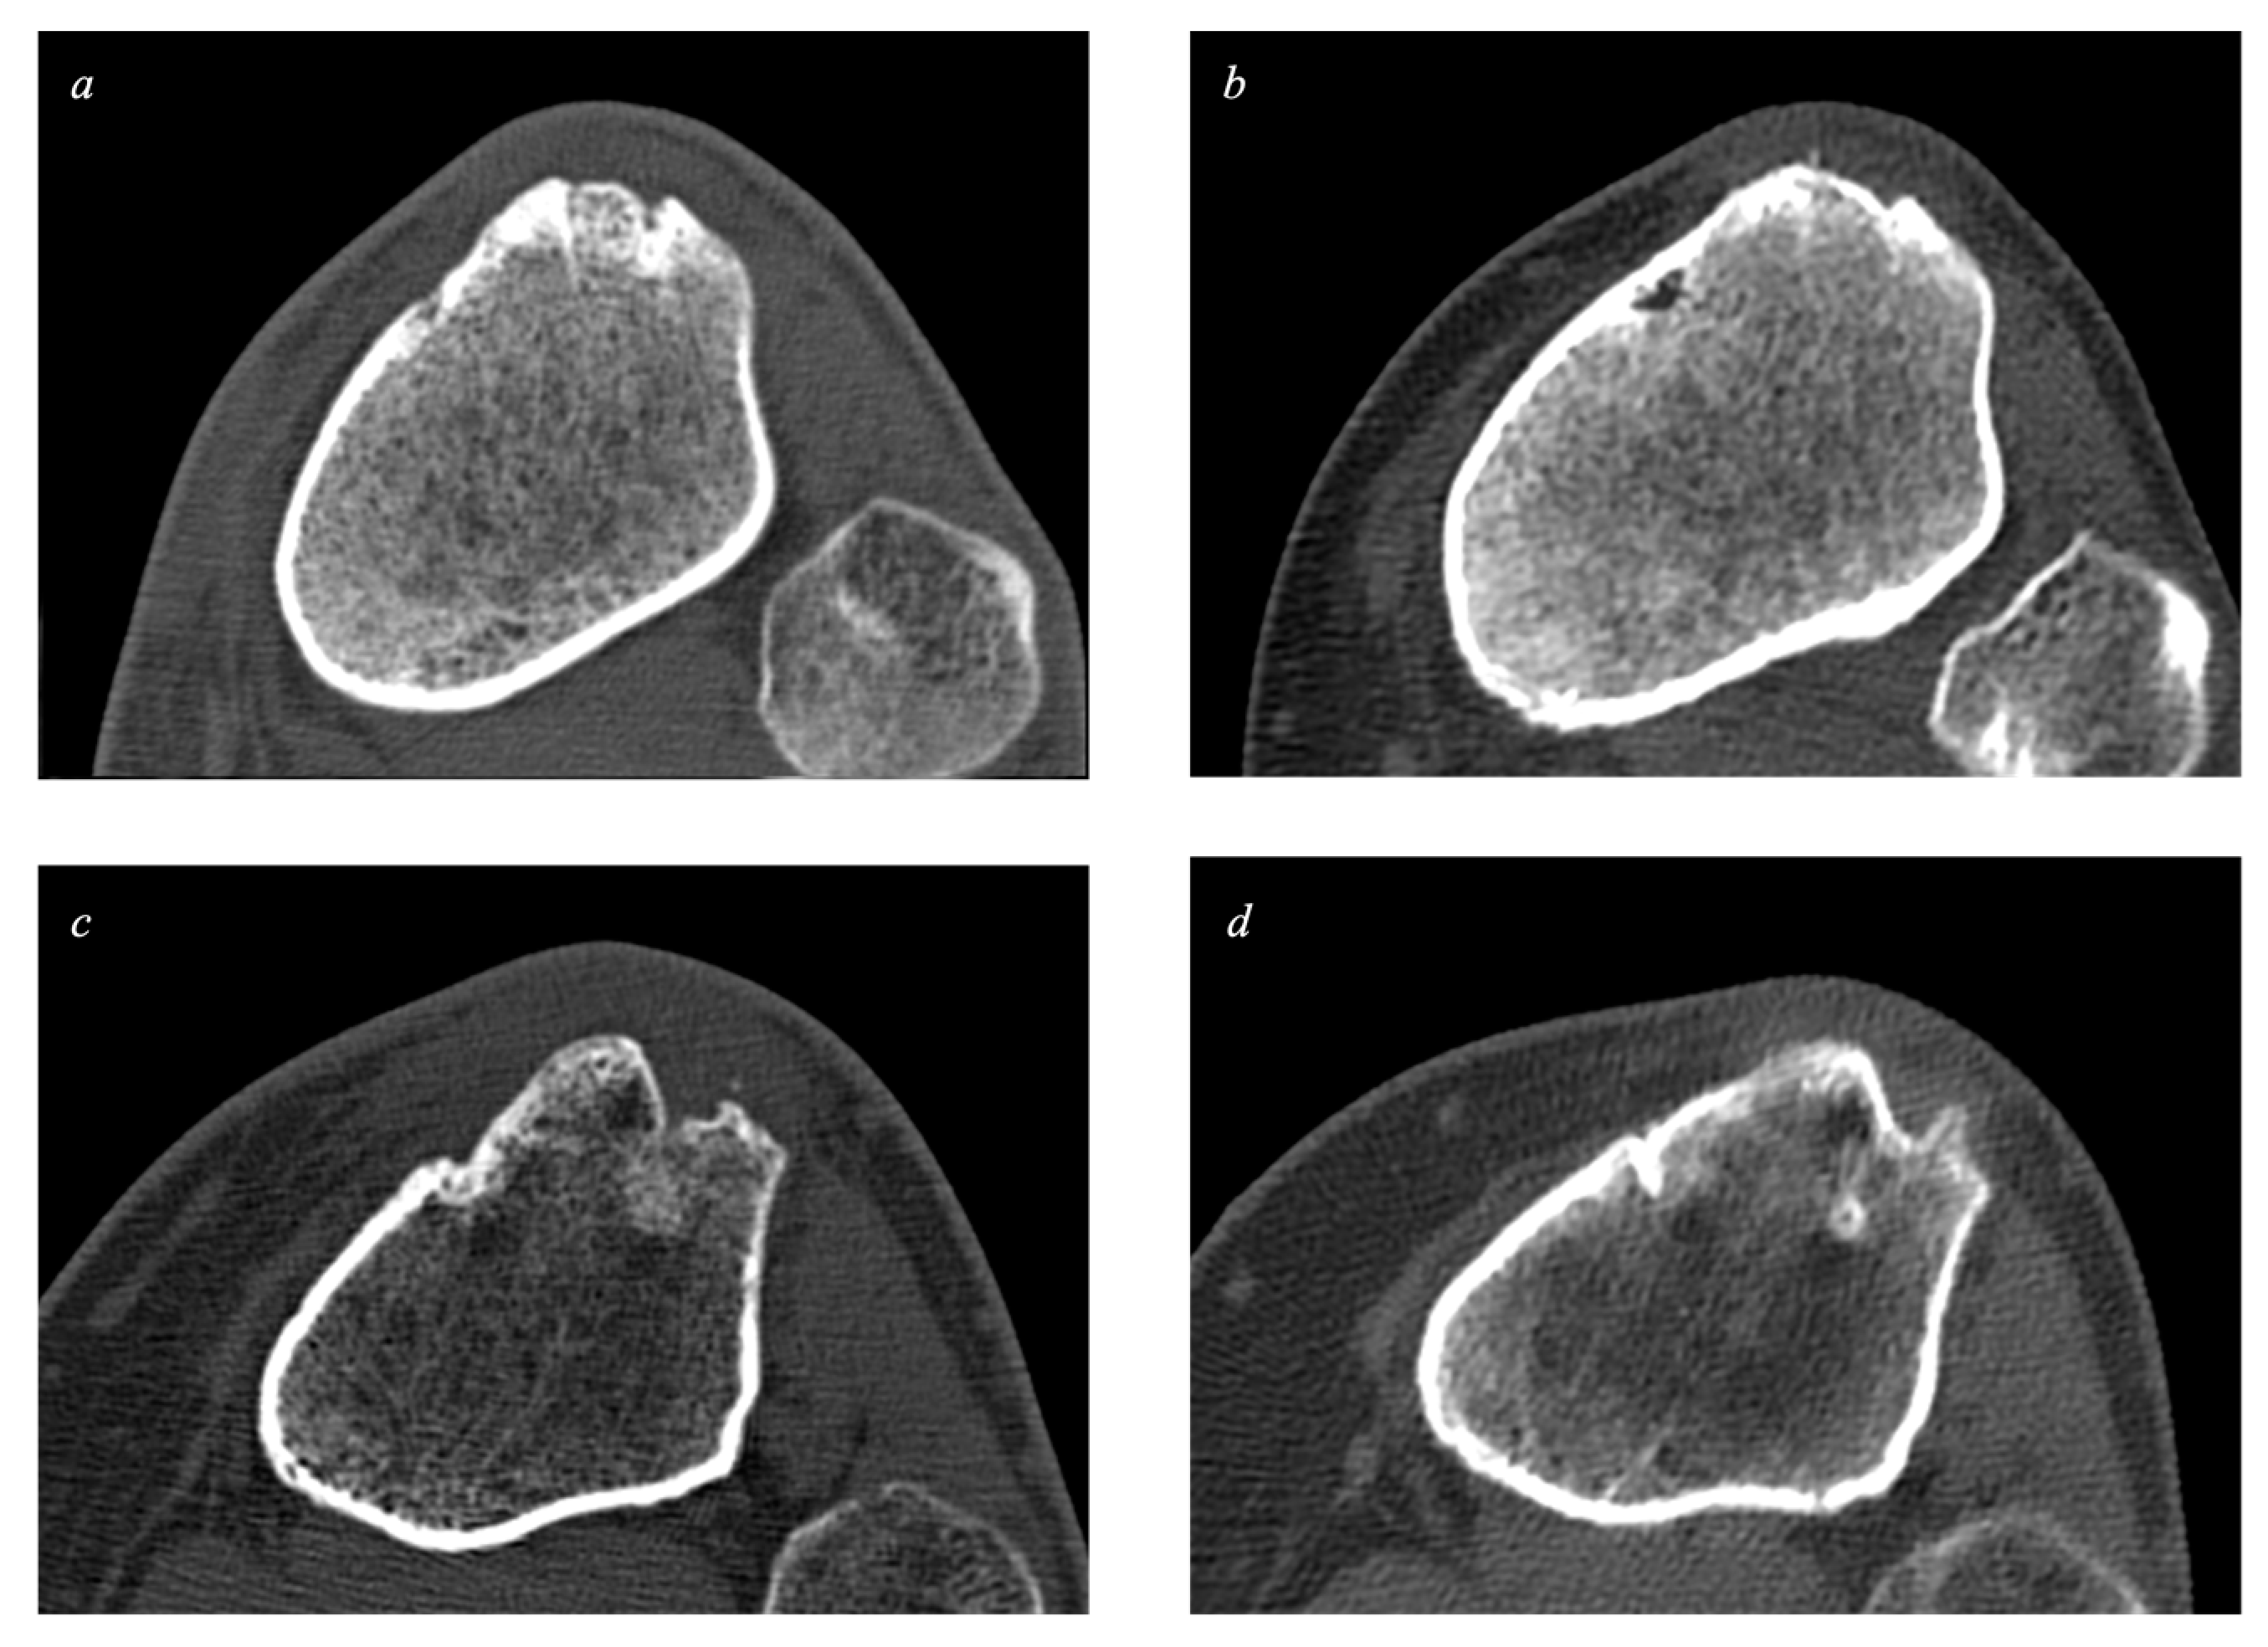

2.2. Bone Quality: Cortical Thickness

2.3. Bone Quality: Subcortical Density

2.4. The Volume of Bone Defects